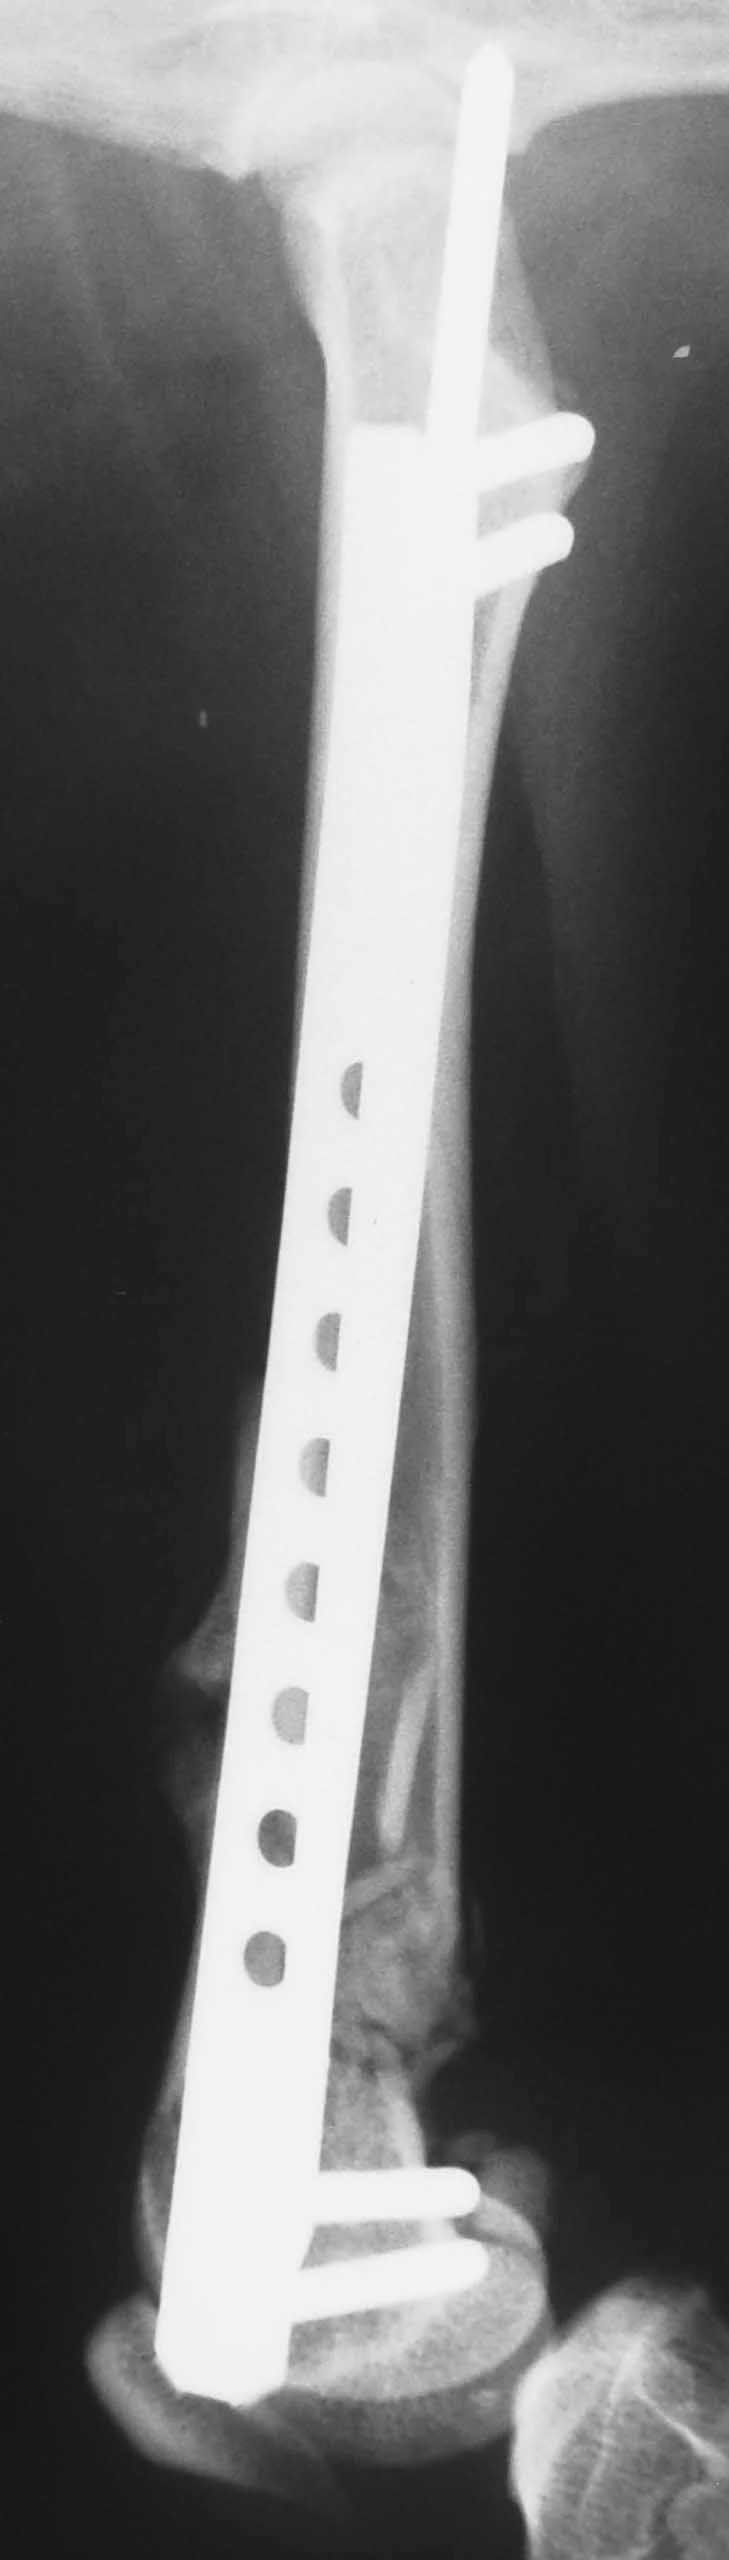

The interlocking-nail system (Innovative Animal Products, Rochester, MN) is another effective implant system for biologic management of comminuted fractures in dogs and cats.1 The interlocking nail is a modified Steinmann pin having transverse holes designed to accommodate screws or bolts. The addition of screws or bolts increases the ability of the pin to resist rotational and compressive forces at the fracture site (Figures 2A, B). This type of fixation is commonly used for stabilization of fractures of the femur and tibia in humans.

Interlocking nails are used in dogs and cats for repair of fractures of the humerus, femur, and tibia. The interlocking-nail system is less expensive than a bone-plate system but has similar biomechanical properties.8 Interlocking nails are easy to apply and are a good option for general practitioners who do not want to invest in a bone-plate system.

Fractures managed using interlocking nails and biologic technique develop extensive bridging callus and early return to function. A minimally invasive surgical approach (note the surgical skin staples) was made to this fracture to minimize disruption of the blood supply to the bone fragment. The fracture fragments quickly become incorporated in the callus if soft tissue attachments can be maintained.

Healing of the comminuted tibial fracture shown in Figures 2A and 2B after stabilization using an interlocking nail system. This fracture reached bony union in 8 weeks.